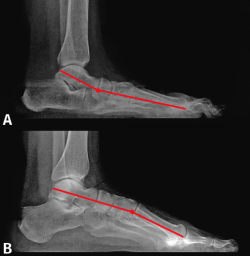

Para ello, se han estudiado radiografías de ambas entidades clínicas. Mediante la línea de Meary(3), que en un pie normal es rectilínea y atraviesa el talus, el navicular y el primer metatarsiano, se ha buscado el punto de rotura o inflexión de dicha línea en pies planos y pies cavos (Figura 1).

Figura 1. Radiografía de perfil en carga. La línea de Meary atraviesa el talus, el navicular, el cuneiforme medial y el primer metatarsiano.

Siguiendo las ideas de Paparella(5), el pie plano presenta en todos los casos una anatomía patológica uniforme: existe un doble movimiento helicoidal o rotatorio en sentido inverso, el retropié está pronado y el antepié supinado, por lo que el primer radio se encuentra en flexión dorsal (Figura 2A). A ello contribuye la pérdida de potencia del peroneo largo, el cual debido al valgo de talón tiene disminuido su brazo de palanca y, por ello, menor fuerza para la flexión plantar del primer metatarsiano. El talus está desplazado hacia abajo, delante y dentro.

M. Núñez-Samper ha estudiado un grupo de pies cavos de diversas etiologías y no encuentra tampoco diferencias morfológicas del CM y de la oblicuidad de la 1.ª ATMT, con relación a un pie normal. Al aumentar la bóveda plantar, el primer metatarsiano se sitúa en flexión plantar, es decir, verticalizado (Figura 2B).